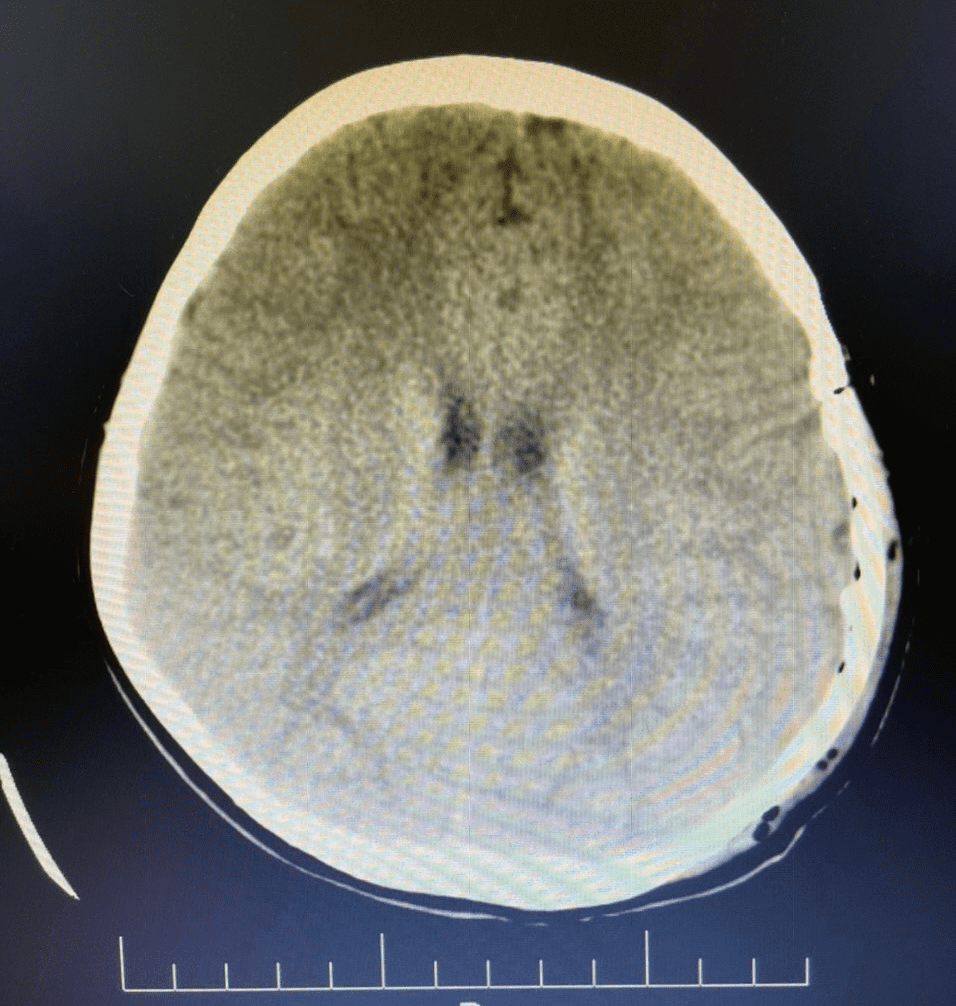

Hình ảnh chụp cắt lớp vi tính của bệnh trước và sau khi mổ chấn thương sọ não

Vào hồi 20h ngày 30/06/2022, Trung tâm y tế thành phố Móng Cái tiếp nhận trường hợp bệnh nhân là cháu N.V.G.B 8 tuổi (Hải Đông- Móng Cái). Trước khi vào viện, bệnh nhân đi xe đạp bị ngã xuống nền cứng, buồn nôn, nôn. Ngay sau khi tiếp nhận, thăm khám, chụp cắt lớp vi tính phát hiện hình ảnh tụ máu ngoài màng cứng, tình trạng tri giác giảm. Kíp trực đã báo cáo lãnh đạo, hội chẩn với bác sĩ chuyên khoa Bệnh viện đa khoa tỉnh, xác định bệnh nhân cần được mổ cấp cứu. Bệnh nhân khẩn trương được hoàn tất các xét nghiệm cận lâm sàng và được chỉ định mổ cấp cứu tại Trung tâm Y tế thành phố Móng Cái ngay trong đêm.